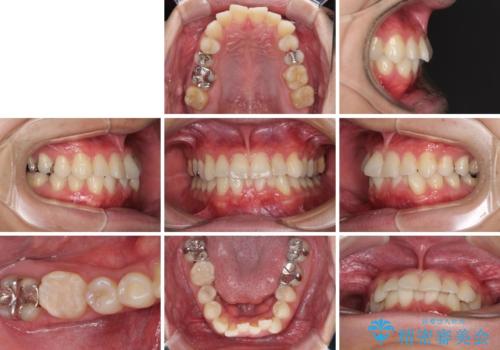

- 30代男性

- 矯正装置

- 審美装置

- 治療期間

- 1年2ヶ月

- 右下奥歯の虫歯がしみて痛いとのことで来院された患者様です。

神経近くにまで及ぶ大きな虫歯でしたが、速やかに処置を行い、痛みは即日解消されました。

虫歯が大きかったため、クラウンによる補綴治療が必要になる旨をお伝えしたところ、矯正治療にも興味があるとのことでした。

短期間で手間のかからない方法がご希望でしたので、ワイヤー装置による矯正治療を行うこととし、矯正治療後に右奥2歯をセラミッククラウンにて補綴することとしました。

セラミッククラウンによる補綴治療と矯正治療の双方が必要となる場合、矯正治療前の処置や歯の移動中に必要な処置など、二種類の治療を同時にチェックすることがとても重要となります。

当法人では、1つの医院で全ての診療を進めることができるため、このような方には大変お勧めです。